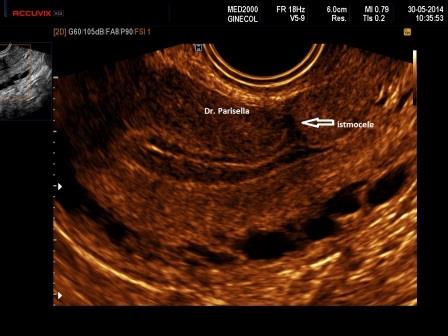

La diagnosi ecografica, essenzialmente effettuata con ecografia transvaginale, anche se in alcuni casi, specialmente nella visualizzazione di eventuali complicanze l'approccio sovrapubico può essere di aiuto ( ndr ), si basa sul riscontro di un'area ecopriva, di profondità almeno 2 mm., più frequentemente a forma triangolare, con apice rivolto verso la parete anteriore dell'utero e base che si continua con la cavità endometriale, localizzata in regione cervico-istmica a livello della cicatrice da pregresso taglio cesareo ( Fig. 1 ).